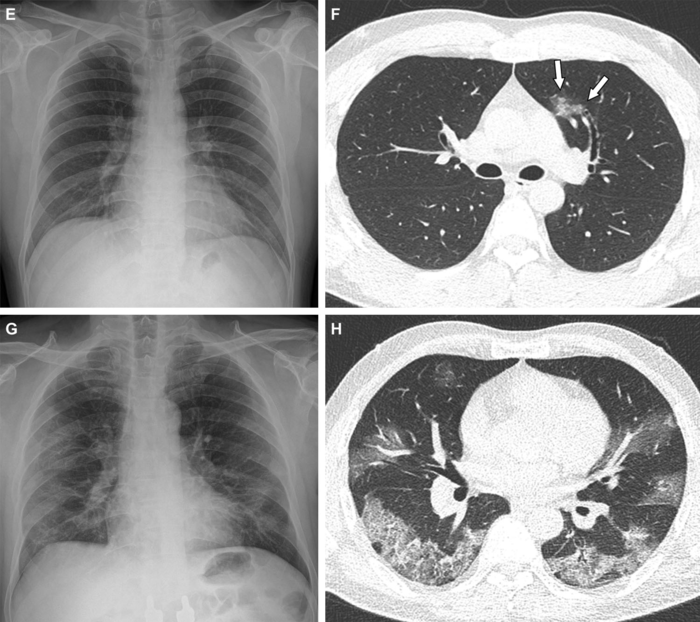

Of the 761 hospitalized patients with COVID-19, the mean age was 47 years, and 385 (51%) were women. Forty-seven patients (6.2%) were fully vaccinated (breakthrough infection), 127 were partially vaccinated (17%), and 587 (77%) were unvaccinated. Chest CT scans were performed on 412 (54%) of the patients during hospitalization. Of patients undergoing CT, the proportion of CT scans without pneumonia was 22% (71/326) of unvaccinated patients, 30% (19/64) of partially vaccinated patients, and 59% (13/22) of fully vaccinated patients. Fully vaccinated status was associated with a lower risk of requiring supplemental oxygen than unvaccinated status, as well as lower risk of intensive care unit (ICU) admission.